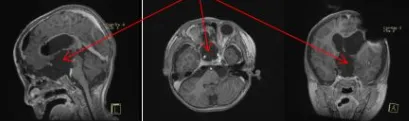

为了保证孩子的安全和高切除率,巴教授教授与Concezio Di Rocco教授决定联合手术,通过额骨颅骨开颅术和大脑半球间穹窿入路肿瘤切除术直至Monro孔(室间孔),并沿着脑室壁向中脑行进。右侧视神经被肿瘤浸润包裹,但是左侧视神经被小心地从肿瘤肿块中剥离出来,垂体腺和垂体柄也被小心保护,无术中并发症。三脑室占位被全部切除,鞍上占位基本全部切除,视神经及周围血管被完整保护。

术后:顺利出院

拔管后,患儿的手臂和腿部移动没有任何问题。在密切监测钠和液体平衡的情况下,调整了去氨加压素药物。回到普通病房后,巴教授与内分泌学家合作,用去氨加压素治疗尿崩症,并优化垂体激素替代。顺利出院后,患儿状况较入院前明显改善。